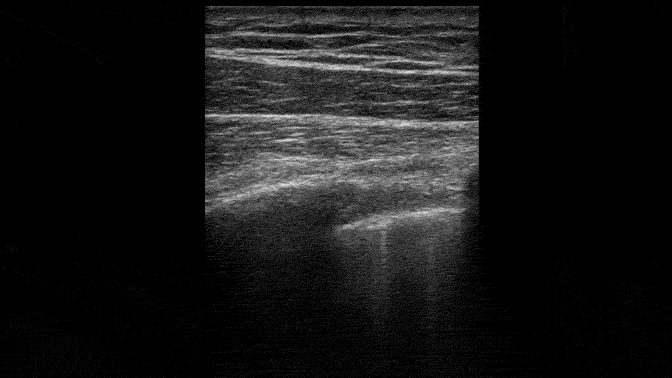

What about this image?

Some of these lines at the pleural surface are bright and seem to go to the edge of this screen. But would they go to the edge of any screen and thus identify themselves as B lines? There is only one way to find out – switch probes and increase the depth.